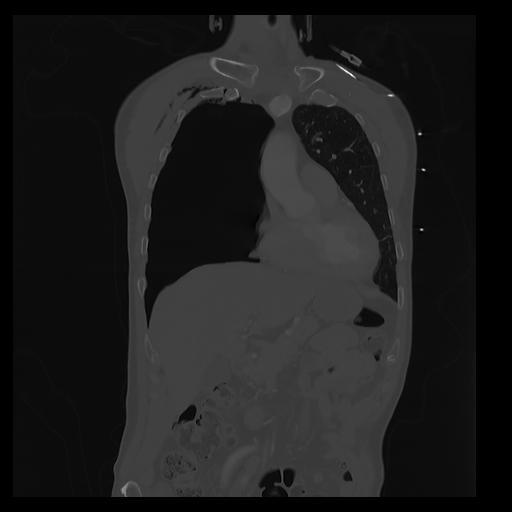

32 PULMON,CE,Coronal,3.000,PULMON,Coronal,